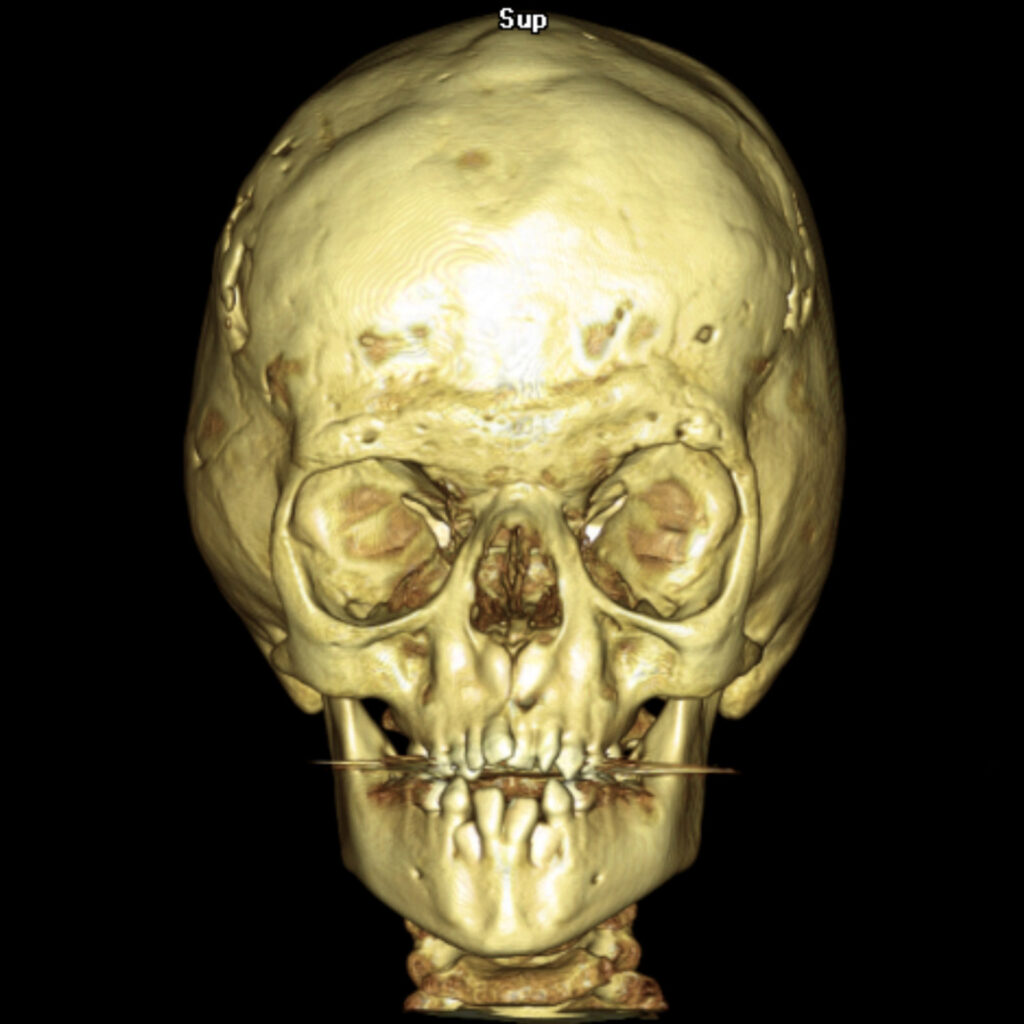

El Síndrome de Apert es un trastorno genético autosómico dominante causado por una mutación espontánea en el gen FGFR2, específicamente en el receptor 2 del factor de crecimiento de los fibroblastos. Esta anomalía genética provoca el cierre prematuro de las suturas entre los huesos del cráneo, una condición conocida como craneosinostosis, afectando la forma de la cabeza y la cara2.

- Craneosinostosis: Cierre prematuro de las suturas craneales, evidenciado por crestas a lo largo de las suturas.

El diagnóstico del Síndrome de Apert se basa en un examen físico detallado, radiografías y pruebas genéticas para identificar la mutación en el gen FGFR2. El tratamiento implica cirugía para corregir craneosinostosis y deformidades en manos y pies. Es crucial la intervención de equipos médicos multidisciplinarios especializados en cirugía craneofacial y genética.